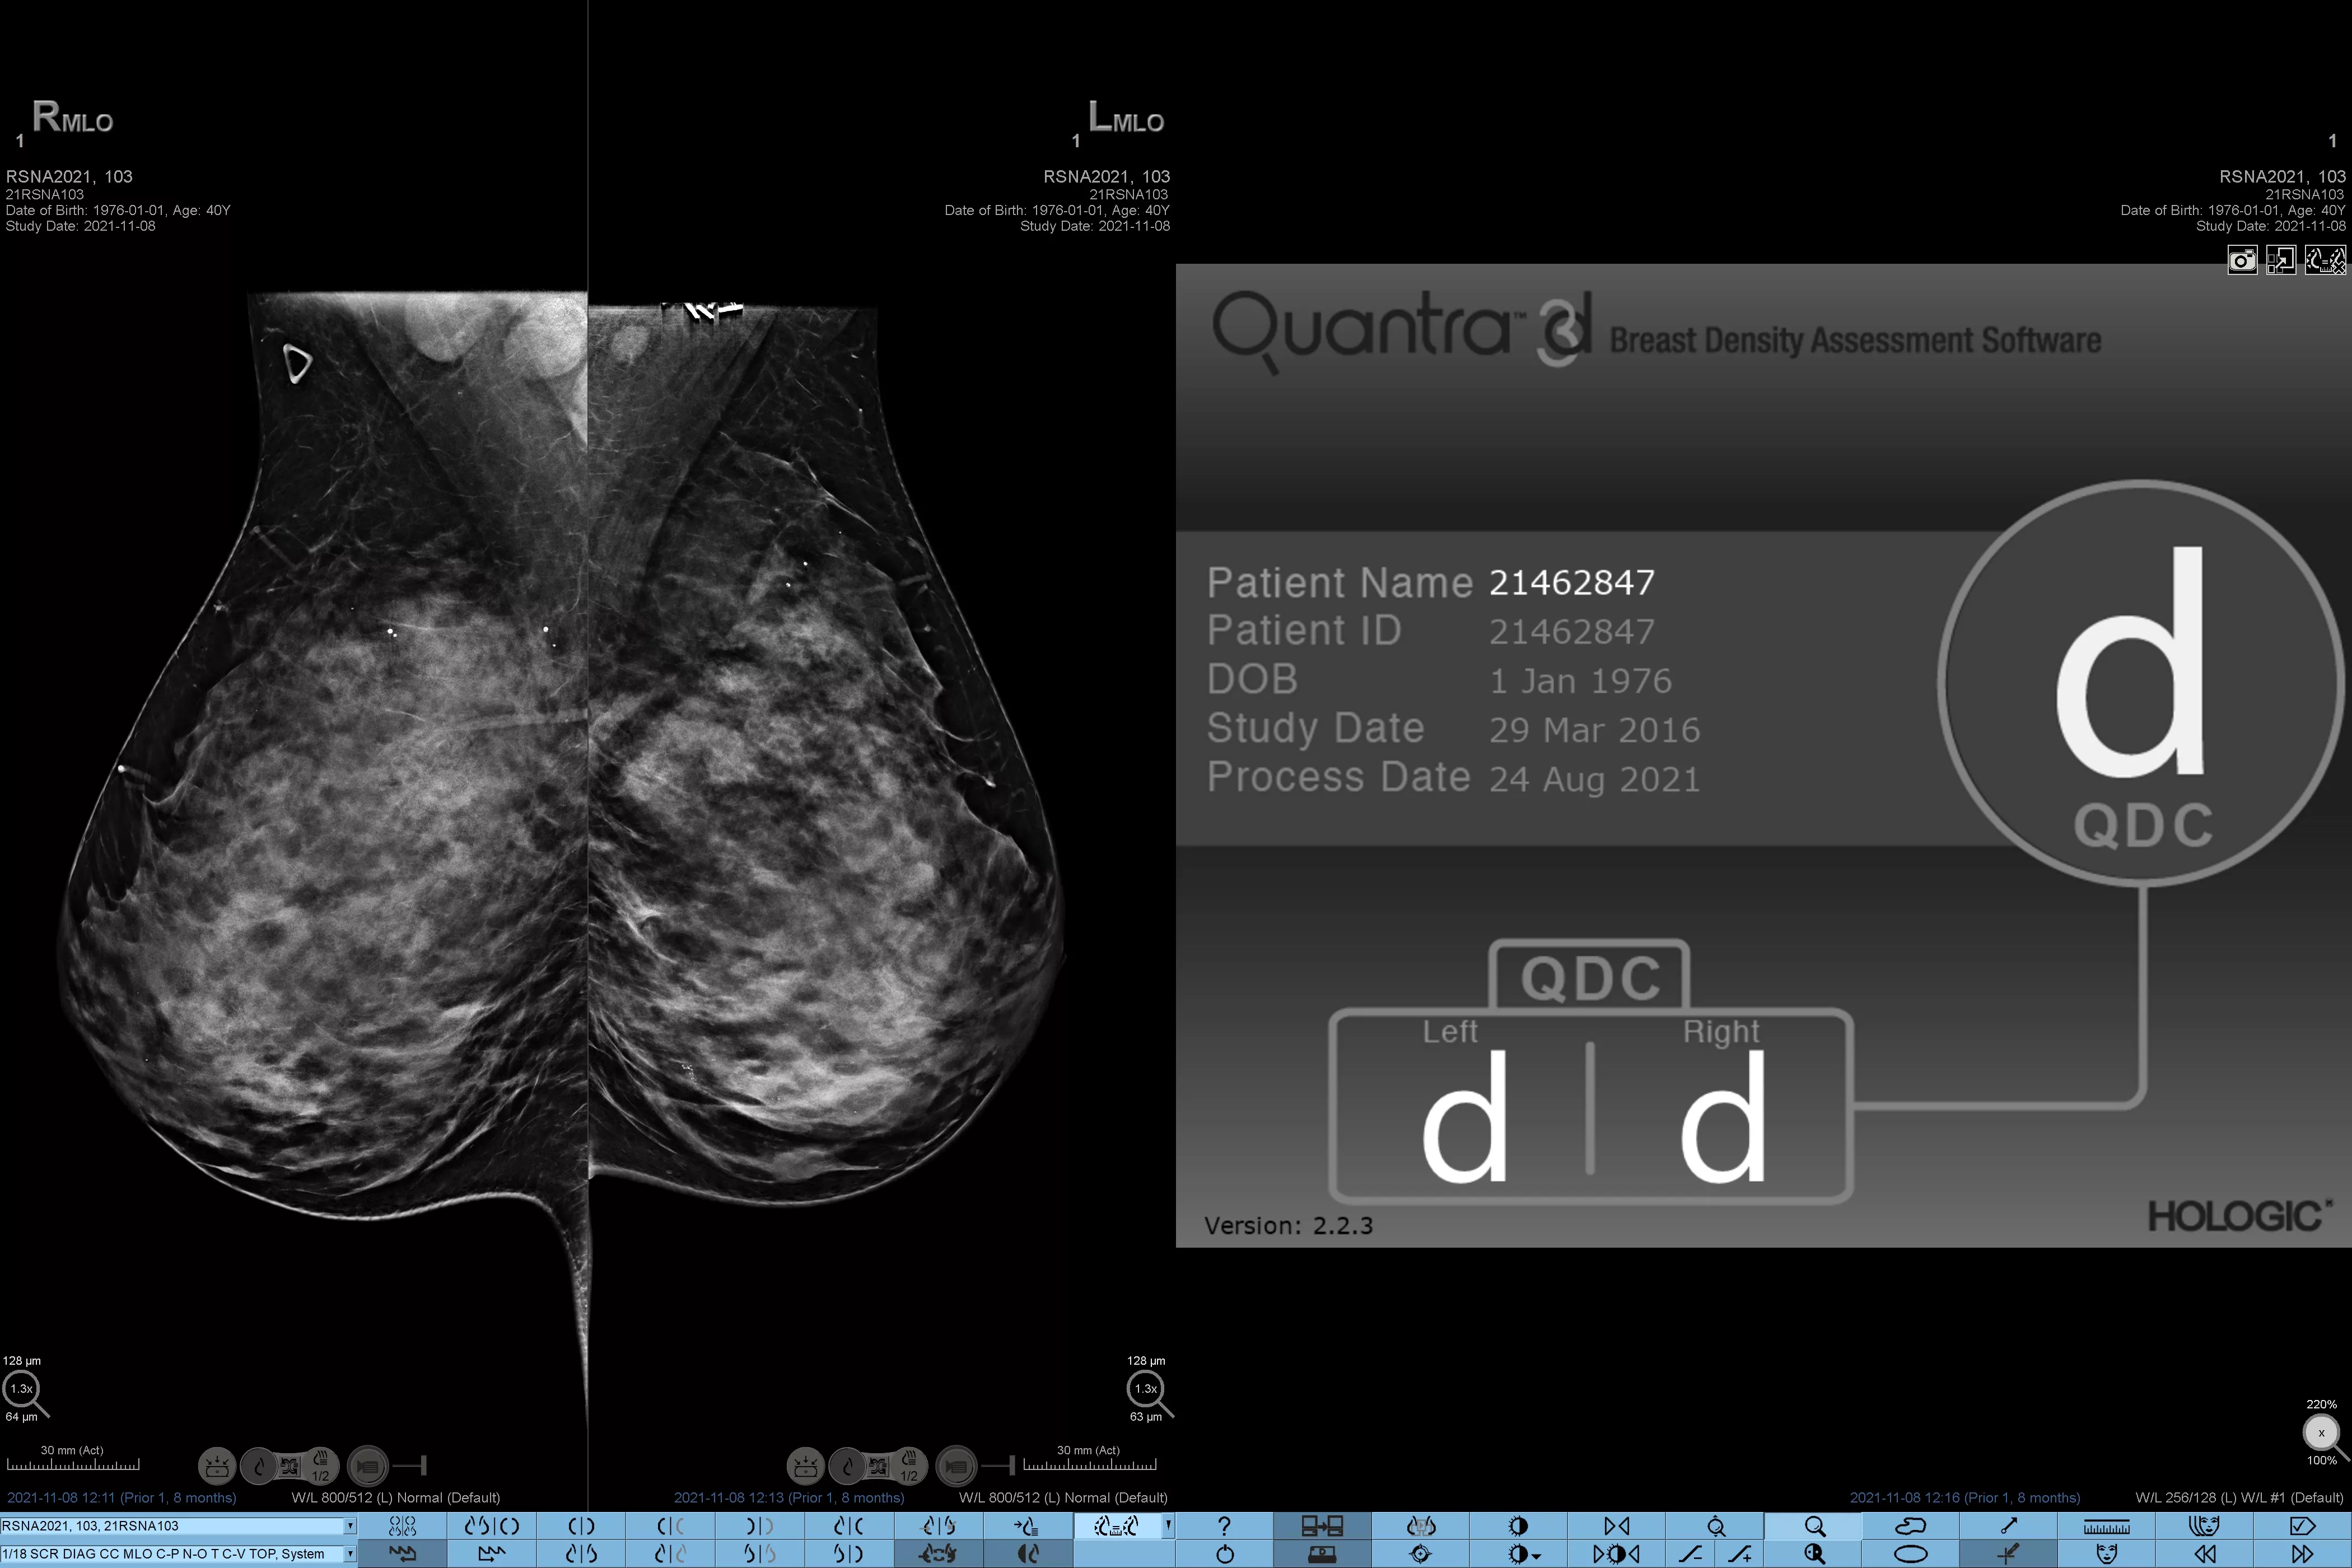

Higher breast density is known to increase a woman’s risk for breast cancer.1 The need for accurate, unbiased analysis is therefore critical. Powered by machine learning, Quantra technology software analyses both 2D™ and tomosynthesis images for distribution and texture of parenchymal tissue. It categorises breasts in four breast composition categories consistent with guidance from the American College of Radiology (ACR) BI-RADS Atlas 5th Edition.2

Objective machine learning algorithm that assigns breast density category based on analysis of breast tissue texture and patterns.

Quantra software’s unbiased algorithm analyse both 2D and tomosynthesis images to support your analysis by:

• Overcoming subjectivity in visual assessment, providing more consistent, and more reliable scoring.*

*Scores are based on ACR BI-RADS categories, in line with the revised guidance by the American College of Radiation (ACR) BI-RADS Atlas 5th Edition. This accounts for pattern and texture, compared with volume, when determining density.